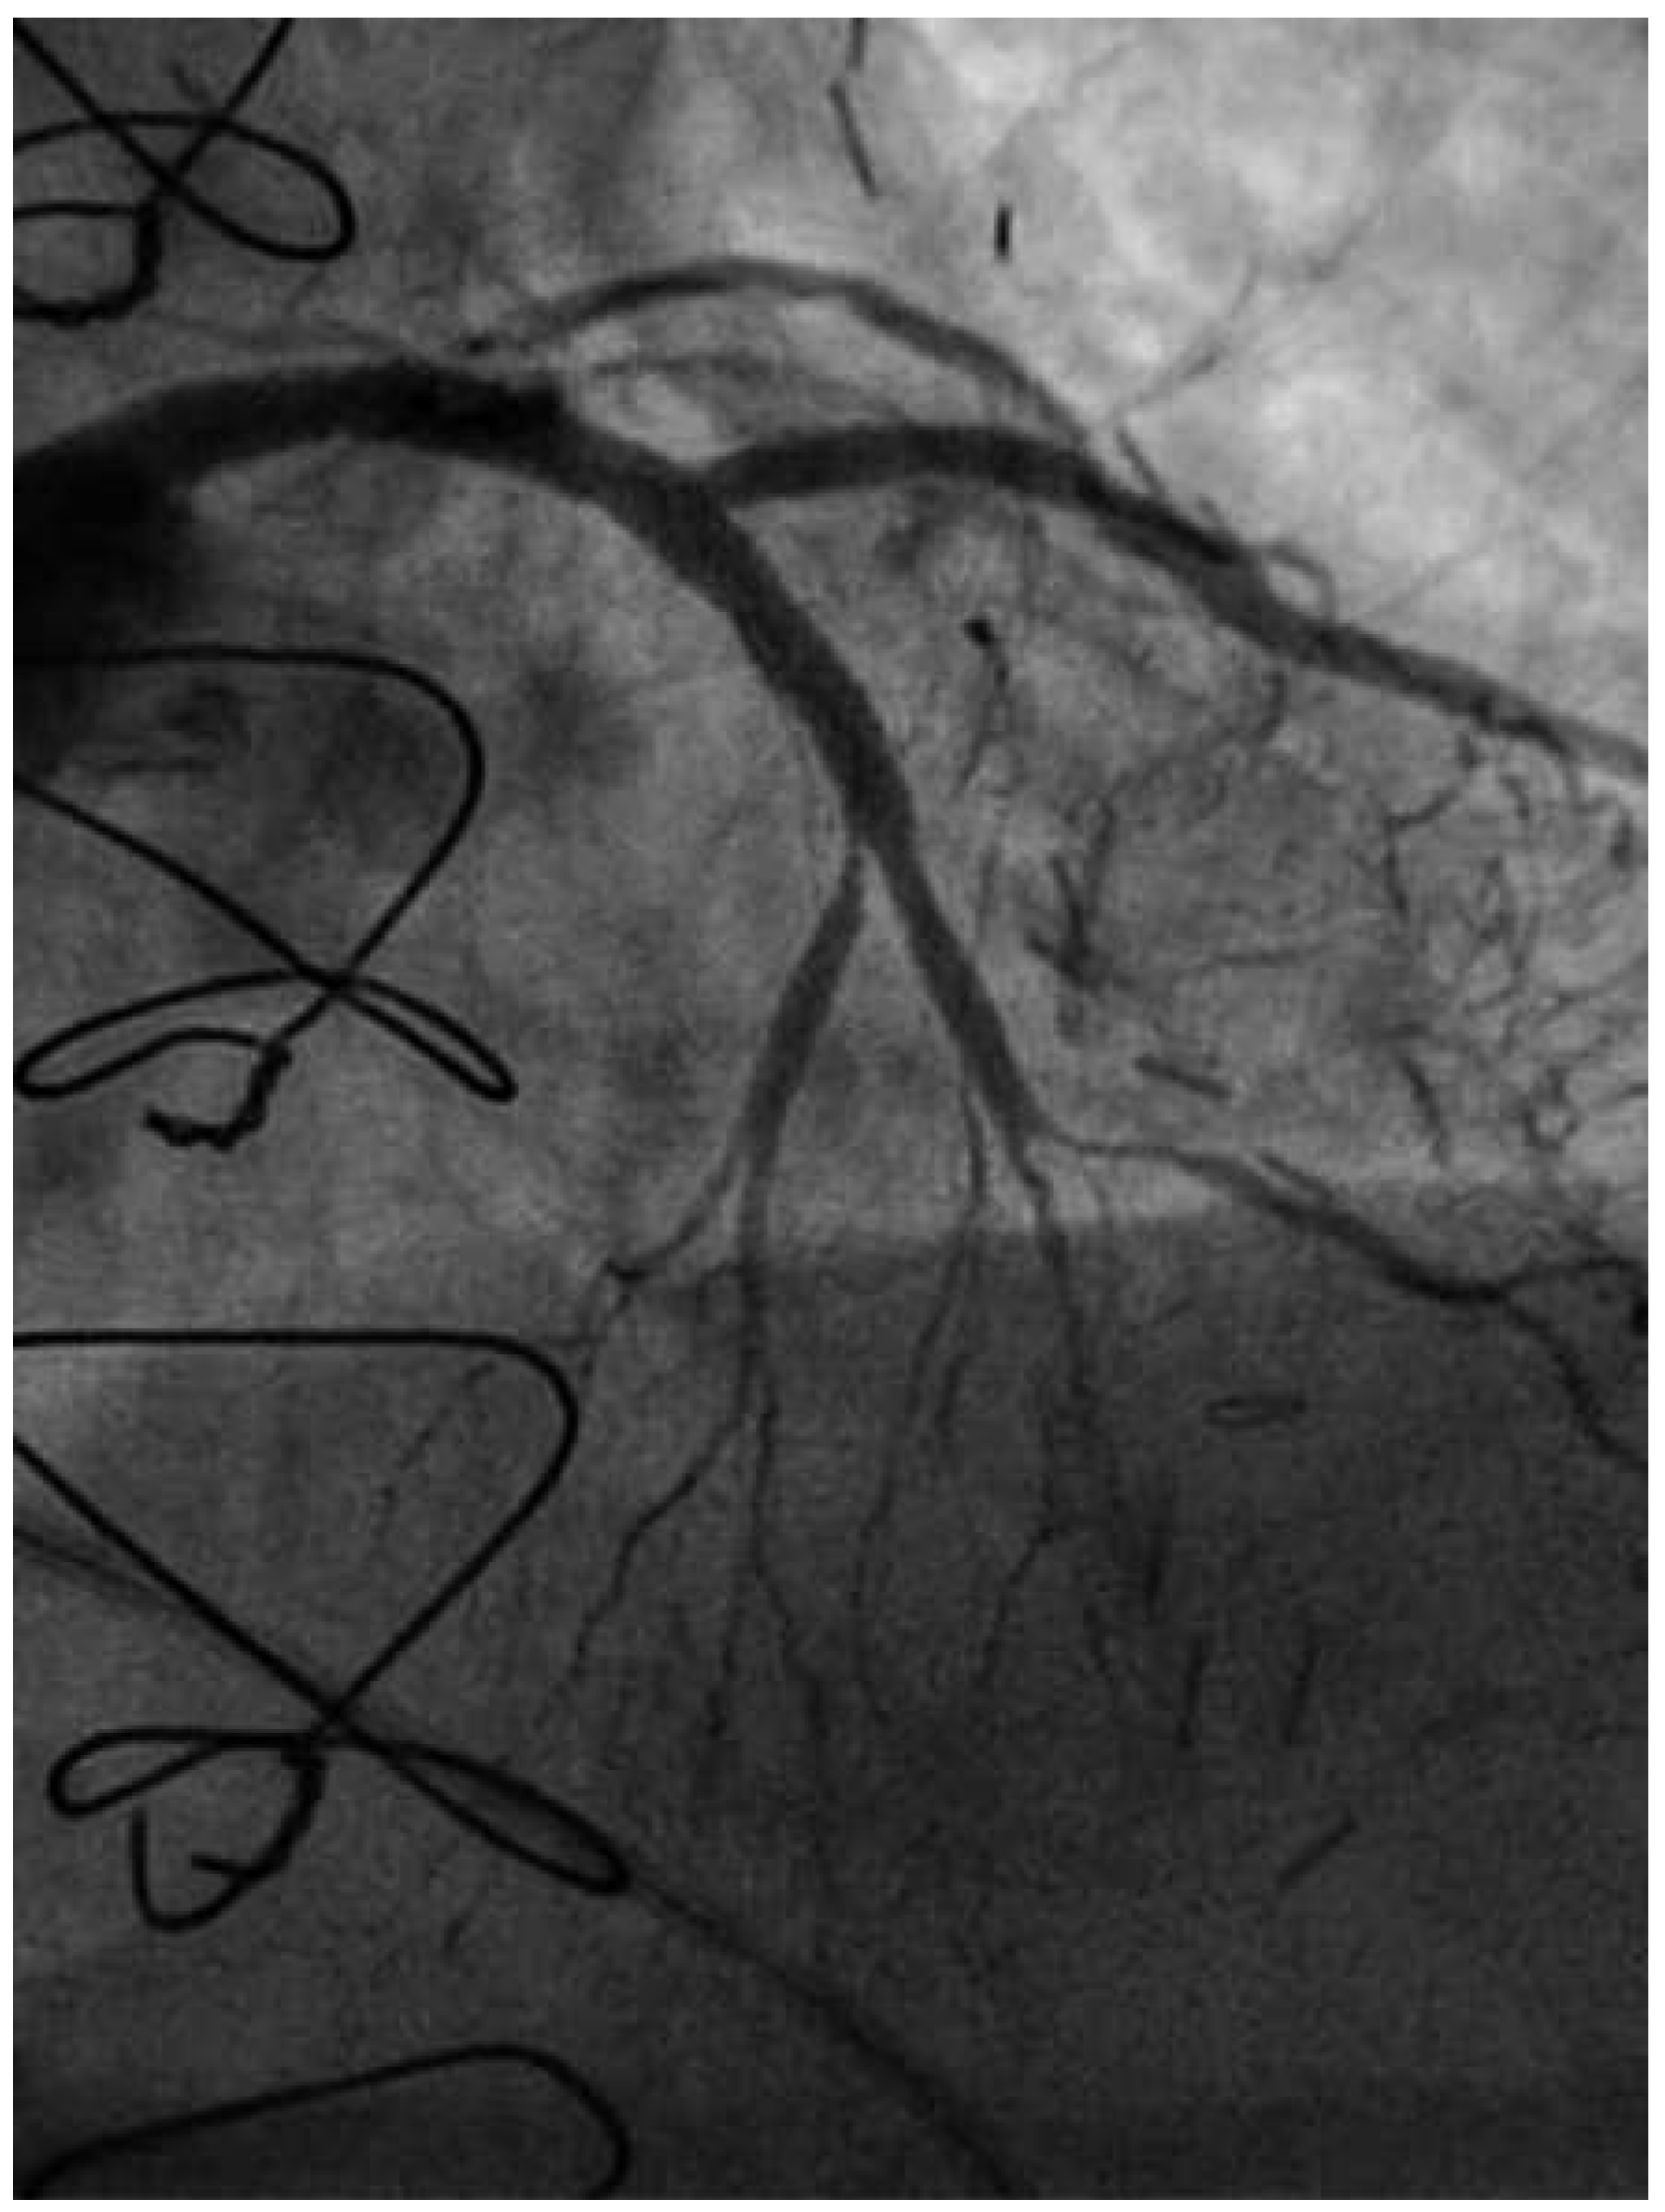

Following RA, both LAD and diagonal were wired with ease using separate Runthrough (Terumo, Japan) wires. Predilatation of both bifurcation limbs was undertaken using 1.5 × 15 mm Trek (Abbott) and 2.0 × 10 mm Sapphire (Orbus-Neich, Hong Kong, China) semicompliant balloons, which both expanded well at nominal pressure. Intending to perform an elective T-stent strategy, a 2.25 × 28 mm Promus Premier DES was deployed at 18 Atm in the diagonal branch, landing proximally at the ostium of this vessel (Figure 3). After removal of the diagonal wire, a 3 × 38 Promus Premier stent (Boston Scientific) was sited from the origin of the LMS across the first diagonal and deployed at 18 Atm (Figure 4). The diagonal branch was then rewired with the runthrough wire. A kissing inflation was performed at 12 Atm using a 3.5 × 12 Quantum (Boston Scientific) and 2.5 × 12 Sapphire noncompliant (NC) balloons in LAD and diagonal, respectively (Figure 5A). The proximal LAD and LMS were then optimised using the 3.5 Quantum NC (LAD) and a Hiryu (Terumo) 4 × 10 NC (LMS) balloons at 22 and 18 Atm, respectively (Figure 5B). The final angiographic result was excellent (Figure 6). Intravascular ultrasound of the LMS was not undertaken as angiographically the LMS stent already appeared completely expanded and oversized. We opted not to intervene in the ostial left Cx in order to best preserve the geometry of the LMS stent.

Figure 6. LAO 30°, cranial 30° views of final angiographic result.